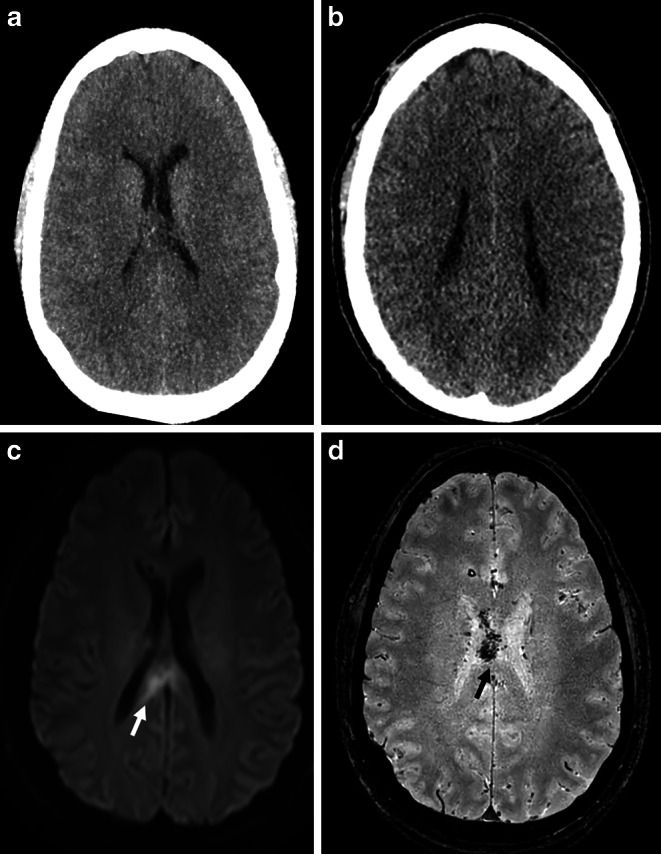

背景:在创伤性脑损伤(TBI)患者中,脱速和加速损伤可引起弥漫性轴索损伤(DAI)。由于缺乏结构异常,在CT上诊断DAI具有挑战性。放射组学是人工智能(AI)领域的一种方法,它提供了从成像数据中提取额外信息的机会。这项工作的目的是评估放射组学与传统放射图像评估相比,对DAI改进诊断的可行性。方法:对42例临床状态怀疑为DAI的患者和2个对照组( = 44;42)行CT和MR影像学检查。DAI由经验丰富的神经放射学家诊断。使用标准化的基于mri的DAI偏好区域图谱提取放射组学特征。不同的基于MRI和CT的模型通过五重交叉验证进行训练和验证。将诊断性能与两位经验丰富的放射科医生的读数进行比较,并在外部测试数据集中进一步验证。结果:DAI患者的MRI和CT模型显示其放射组学特征与对照组有显著差异。所开发的基于MRI的随机森林分类器的准确率为80-90%。表现最好的CT模型在训练数据中的准确率为88%,在外部测试数据中的准确率为70%。结果与传统图像分析相当,基于ct的诊断准确率为70-81%。结论:基于MRI和ct的放射组学分析是评估DAI的可行方法。放射组学分类器达到了与视觉放射图像诊断相当的性能率。特别是基于放射组学的CT分类器可以作为TBI患者的筛查和基于人工智能的决策支持工具,具有临床价值。